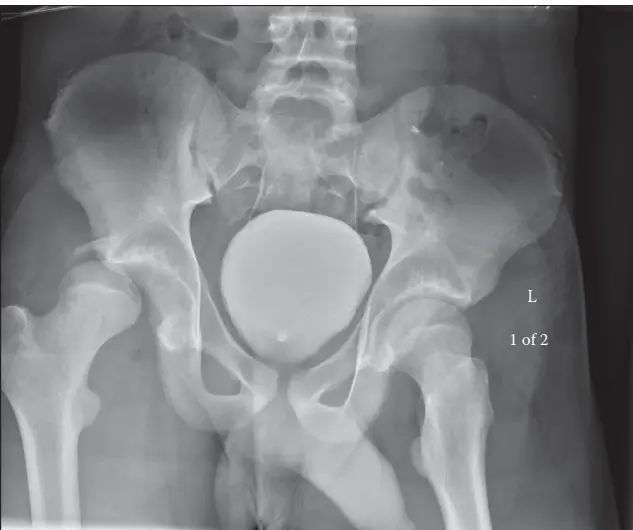

-

الأشعة السينية (X-rays):

- الأشعة الأمامية الخلفية (AP view): تُظهر بوضوح خروج رأس عظم الفخذ من الحُق، وموقعه الخلفي.

- الأشعة الجانبية (Lateral view): تساعد في تأكيد الاتجاه الخلفي للخلع وتحديد وجود أي كسور مصاحبة.

- أشعة الحوض المائلة (Oblique views/Judet views): تُستخدم لتقييم الحُق بدقة والكشف عن الكسور التي قد لا تظهر في الأشعة العادية.

- يستخدم الدكتور هطيف الأشعة السينية فوراً لتأكيد الخلع واستبعاد أي كسور عنقية قد تعيق الرد المغلق.